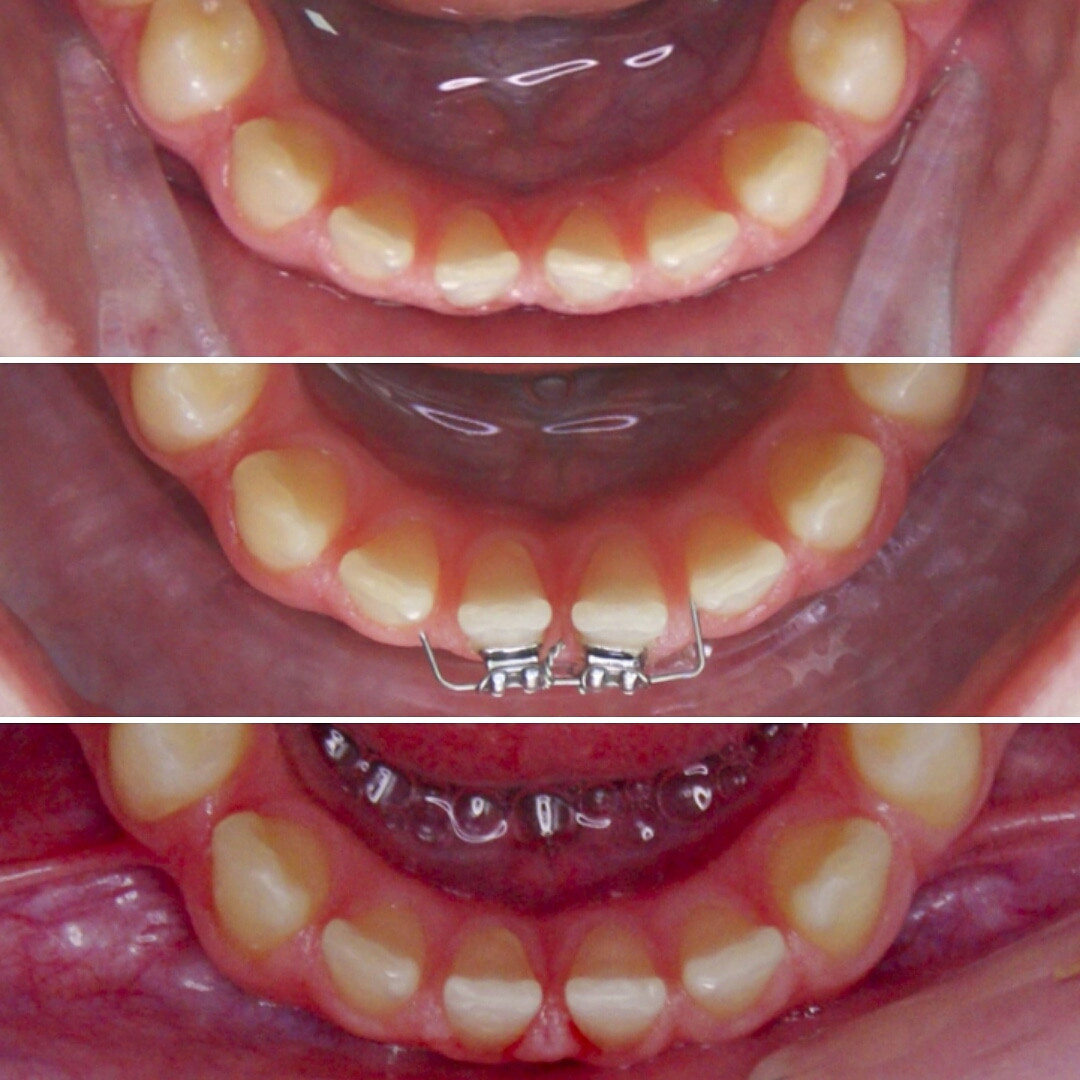

Эта фраза знакома многим ответственным родителям, которые привели на приём к ОРТОДОНТУ своего ребёнка в 5-10 лет, заподозрив проблему или понимая, что места постоянным зубам откровенно не хватает! Горькая правда в том, что брекеты - не волшебное средство от всех проблем, они "расставляют" зубы внутри сформированого объёма челюсти, но никак не влияют на её рост. Родители ждут, а тем временем драгоценное время, когда ребёнок растёт, уходит... Во взрослом возрасте приходится удалять здоровые зубы или прибегать к ортогнатической хирургической операции. 📸 На фото узкая нижняя челюсть, места постоянным зубам нет, боковые резцы прорезываются "вторым рядом".

❓Ну что? Будем ждать 12 лет? Или будем помогать ребёнку?

✅ Помогаем с помощью расширяющей дуги, пружины и зацепных элементов, которые зафиксированы на МОЛОЧНЫЕ зубы